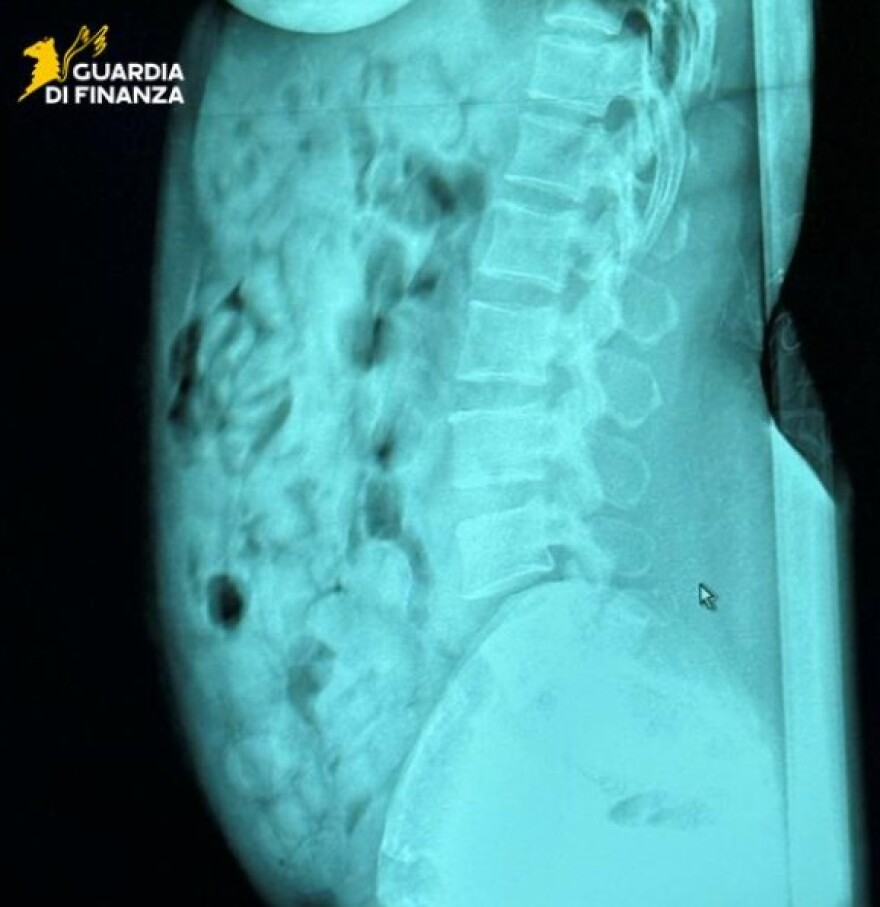

Ακτινολογικές εξετάσεις στο νοσοκομείο του Μπέργκαμο επιβεβαίωσαν την παρουσία ναρκωτικών, τα οποία ήταν σφραγισμένα με κολλητική ταινία. Μετά την αποβολή τους, η ουσία κατασχέθηκε και η γυναίκα οδηγήθηκε στη φυλακή του Μπέργκαμο, στη διάθεση της δικαστικής αρχής.

Δείτε φωτογραφία: